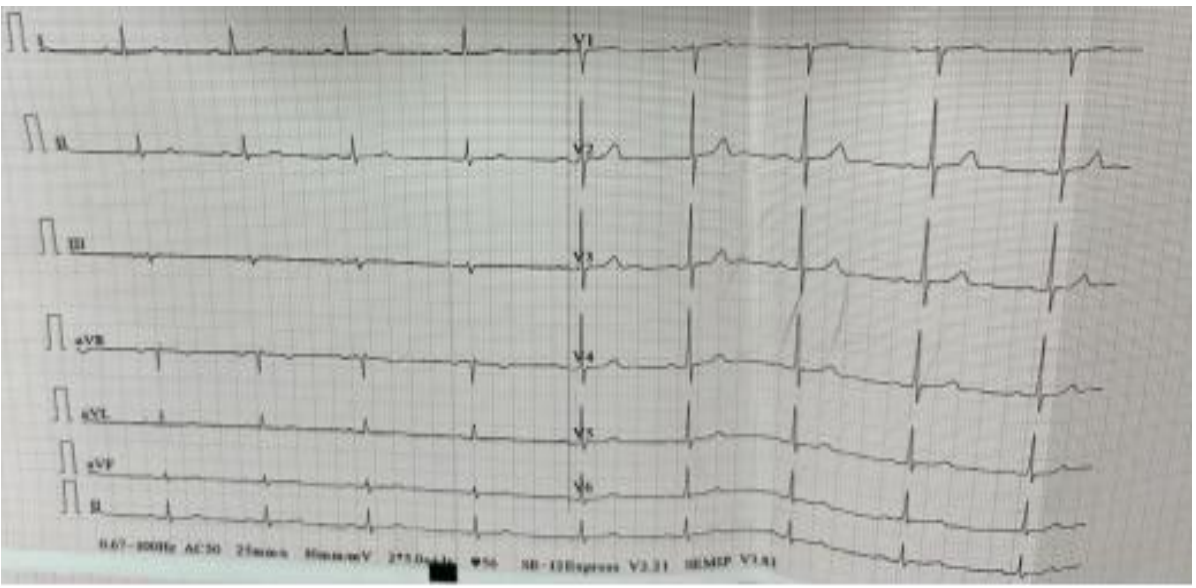

Consequently, treatment with Methimazole (Dimazole) 10 mg/day was initiated. Daily ECG monitoring showed no recurrence of high-degree AVB following initiation of antithyroid treatment.

Figure 2. ECG after initiation of antithyroid drug therapy

A 48-hour ECG Holter performed on day 7 of treatment showed sinus rhythm without any episodes of atrioventricular block of any degree. Thyroid function tests had normalized, with TSH at 0.5 mIU/L and free T3 at 4 ng/L.